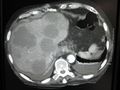

صورة أشعة مقطعية لانبثاثات متعددة بالكبد